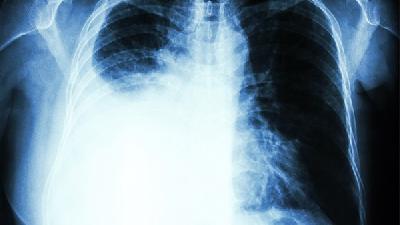

小支原体肺炎可通过大环内酯类抗生素、四环素类抗生素、氟喹诺酮类抗生素、对症支持治疗等方式治疗。小支原体肺炎通常由支原体感染、免疫力低下、接触传染源、合并基础疾病等原因引起。

1、大环内酯类抗生素

阿奇霉素、克拉霉素、罗红霉素等药物可抑制支原体蛋白质合成。支原体感染可能与环境暴露、飞沫传播有关,常表现为刺激性干咳、低热。

2、四环素类抗生素

多西环素、米诺环素适用于对大环内酯类耐药病例。免疫力低下可能与疲劳、营养不良相关,易出现反复发热、咽痛症状。

3、氟喹诺酮类抗生素

左氧氟沙星、莫西沙星用于成人患者,儿童禁用。接触传染源多发生在学校等聚集场所,可伴随头痛、肌肉酸痛。

4、对症支持治疗

布洛芬退热、氨溴索祛痰、雾化吸入缓解气道痉挛。合并慢阻肺等基础疾病时需加强氧疗监测,警惕呼吸衰竭。

治疗期间保持室内空气流通,适量增加饮水,选择易消化高蛋白饮食,恢复期避免剧烈运动。